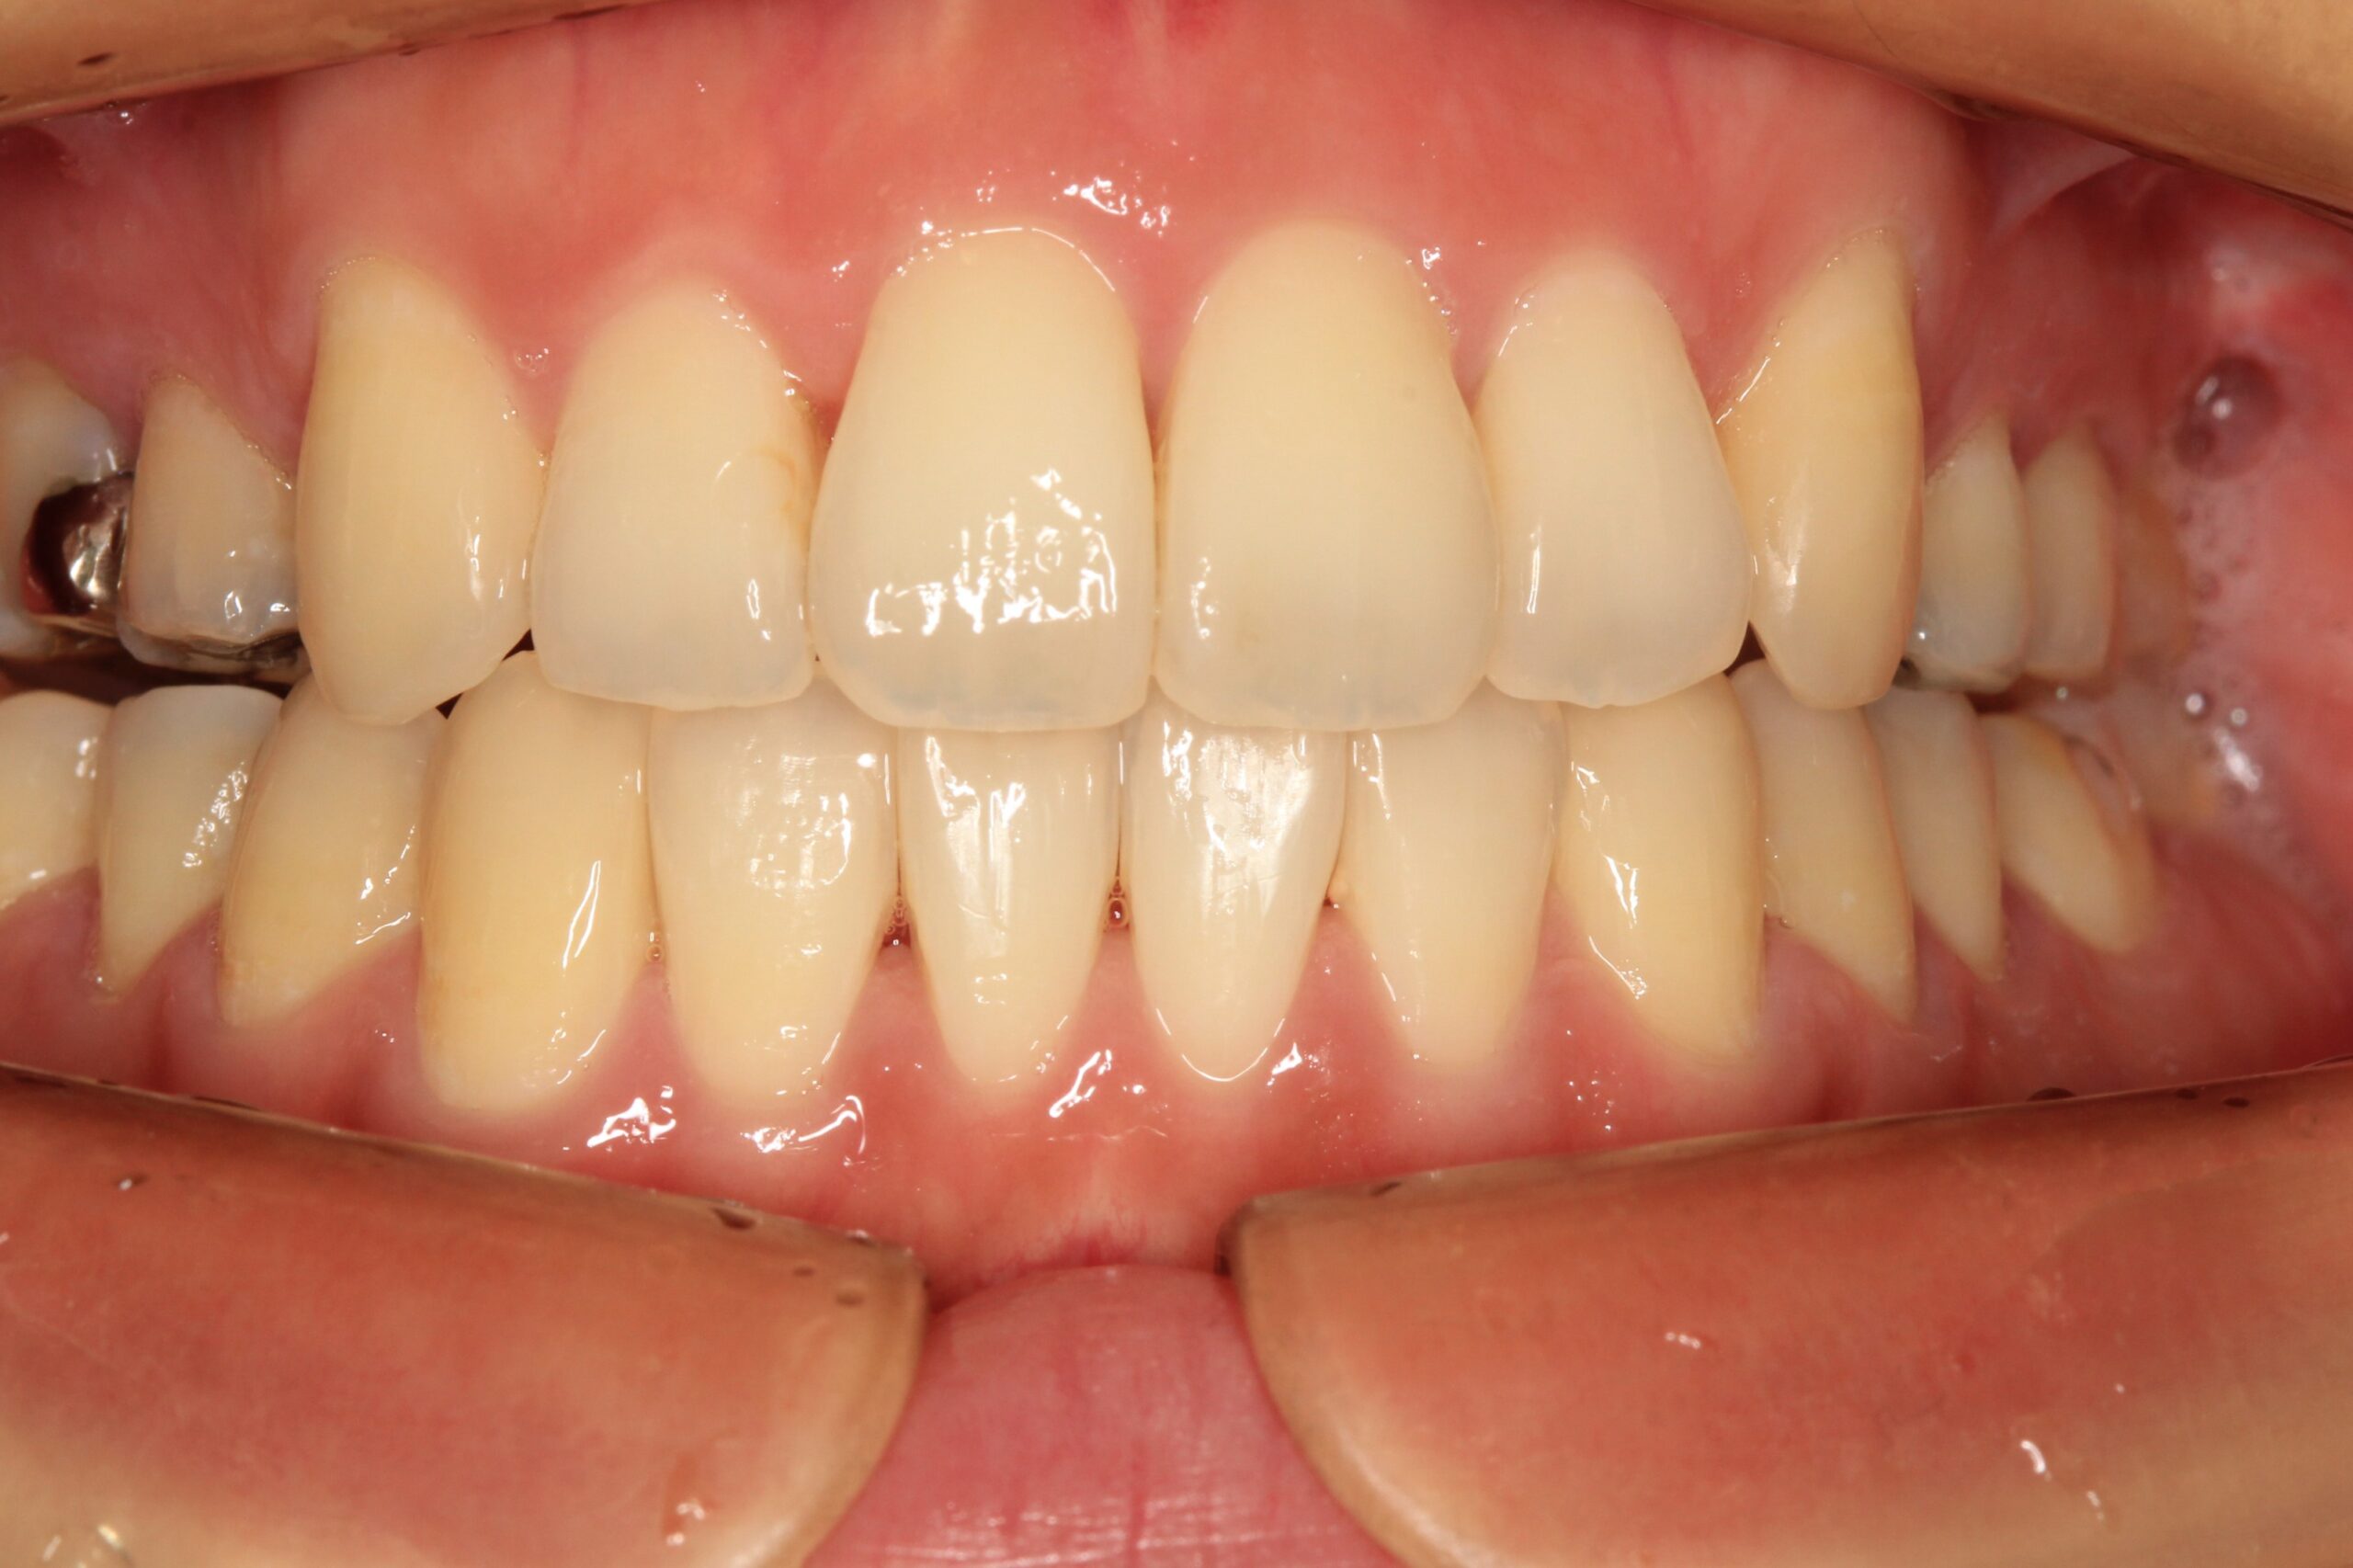

出っ歯も綺麗に引っ込み、開咬も綺麗に改善しました。

今回のケースは出っ歯と開咬の同時改善です。

上顎左右の小臼歯を抜歯を行った関係上、通常なら3年はかかるケースですがインビザラインと加速矯正装置を使用することで約1年6ヵ月位で終了致しました。